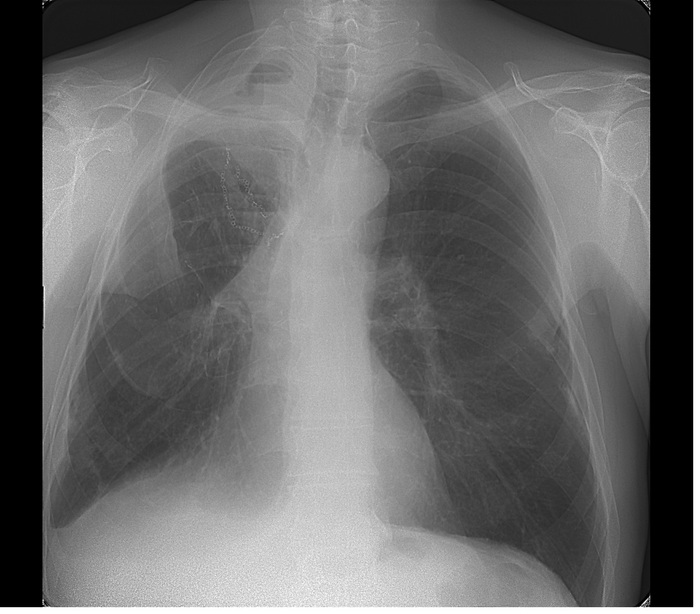

Расшифровка цифровых кодов флюорографии с примерами

01 - Кольцевидная тень (полость).

02 - Затемнение в легочной ткани (инфильтрация,ателектаз, округлая тень, среднедолевой синдром и др.).

03 - Очаговые тени в легочной ткани.

04 - Расширение тени средостения, в том числе увеличение размеров корня.

05 - Плевральные выпоты.

06 - Фиброзные изменения в легочной ткани (выраженные).

07 - Фиброзные изменения в легочной ткани (ограниченные).

08 - Повышение прозрачности легочной ткани (эмфизема локальная и распространенная).

09 - Изменения плевры (сращения, плевральные наслоения, обызвествления) выраженные.

10 - Изменения плевры (сращения, плевральные наслоения, обызвествления) ограниченные.

11 - Петрификаты крупные в легочной ткани - множественные (5 и более).

12 - Петрификаты крупные в корнях - множественные (5 и более).

13 - Петрификаты мелкие в легочной ткани - множественные (5 и более).

14 - Петрификаты мелкие в корнях - множественные (5 и более).

15 - Петрификаты крупные в легочной ткани - единичные.

16 - Петрификаты крупные в корнях - единичные.

17 - Петрификаты мелкие в легочной ткани - единичные.

18 - Петрификаты мелкие в корнях - единичные.

19 - Изменения диафрагмы, не связанные с плевральной патологией (диафрагмальная грыжа, высокое стояние диафрагмы и т. д.).

20 - Состояние после операции на легком.

21 - Изменения скелета грудной клетки (сколиоз, кифосколиоз, костная мозоль, добавочное ребро, остеофиты и т. д.).

22 - Инородное тело (проецируется на легочную ткань, тень средостения в мягких тканях).

23 - Сердечно-сосудистая патология.

24 - Прочие - добавочная доля.

25 - Норма.

26 - Брак.

Примечания:

При сочетании нескольких из перечисленных изменений каждое из них отмечается соответствующим кодом в каждой графоклетке.

Локализация, протяженность изменений отмечается дробью по второй графоклетке 1; 2; 3; 4; в числителе - правое легкое, в знаменателе - левое легкое (по полям).

Номер шифра легочных полей: 1 - первое, 2 - второе, 3 - третье, 4 - первое и второе, 5 - первое и третье, 6 - второе и третье, 7 - первое, второе и третье.

В третьей графоклетке вместо подписи врача подставляют личный номер рентгенолога.

Вызов на контрольное рентгеновское дообследование отмечается в четвертой графоклетке цифрой 1.